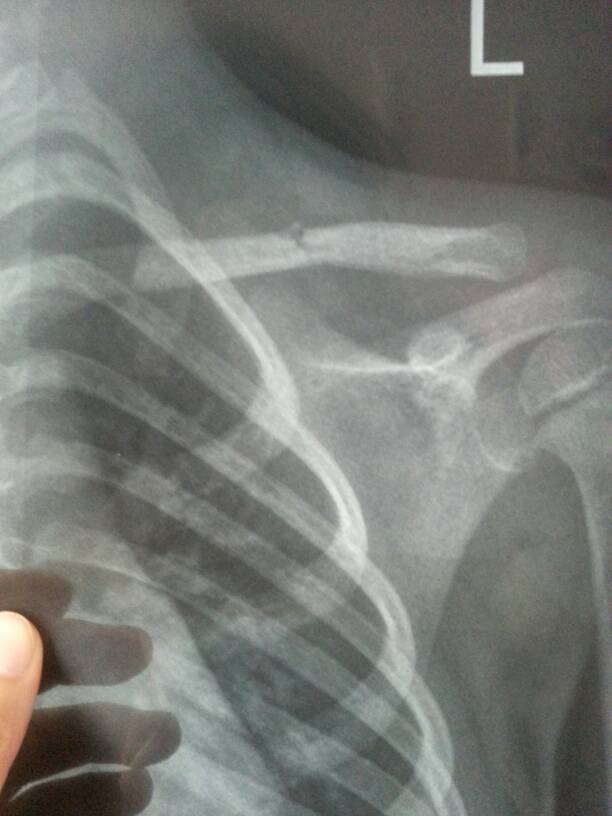

三岁半宝宝从床上掉下来造成左侧锁骨断裂,医生说不需要固定,开了两盒药让宝宝回家静养 现在孩子在床上 三岁半宝宝从床上掉下来造成左侧锁骨断裂,医生说不需要固定,开了两盒药让宝宝回家静养。现在孩子在床上躺了一周了,请问可以让孩子坐起来,或者做其他轻微的活动吗?又怕因为没有固定让她起来骨头会长不好。 点击展开 匿名用户 2014-08-05 10:52 为您推荐: 其他回答 你好,这个是不用担心的呢,自己这个时候是要多注意去检查一下身体的呢,这样是会更好一些的啊 可靠的悠闲80 2014-08-05 14:28 相关问题 我家宝宝7岁,让轮胎砸的头部颅骨骨折,没有出血点,医生建议回家静养,我该怎么做,孩子回答问题清晰 有心把婆媳关系搞好不过真心累 我现在怀孕了而且见红了还开了个店,没有办法我只能在床上静养,第三天不流血了又躺了4天婆婆就想我下去看店 保胎一定要平躺吗?现在在保胎期间一直都躺在床上静养没有出门了